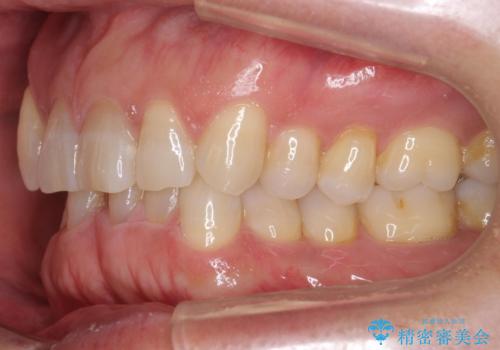

八重歯と下の歯のがたつき マウスピースで

- 右上の犬歯が目立つのが気になる、下の歯並びも治したいとのことで来院。

歯を抜かずに少し削って小さくして並べました。

並びも良くなり、患者様にも喜んでいただきました。

右上の犬歯の歯肉退縮自体は進行する可能性をお伝えしておりましたが、特に変化なく治療できました。

歯肉退縮につきましては、歯ぐきの移植を提案しましたが特に希望されませんでした。